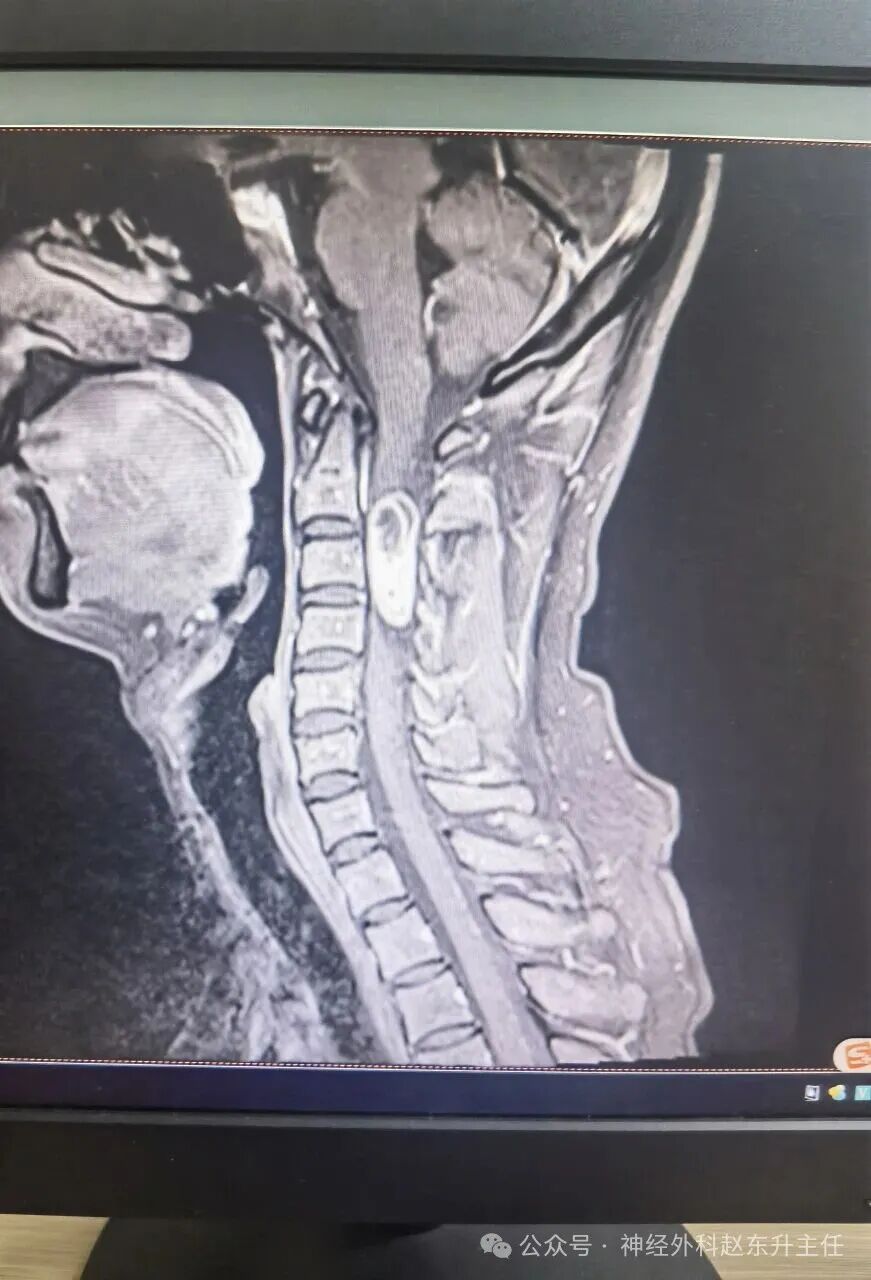

脊髓畸胎瘤该怎么办?

“脊髓畸胎瘤”是一个比较复杂的诊断,听到这个词肯定会让人非常担忧。但请先不要过度焦虑,这是一个相对罕见的疾病,其处理需要非常专业和个体化的方案。

· 脊髓畸胎瘤:就是这种肿瘤长在了脊髓或椎管内。它可能是良性的,也可能是恶性的。

核心处理原则:手术切除是根本。

无论良恶性,手术都是首选且最核心的治疗手段。 治疗目标是尽可能完整地切除肿瘤,解除对脊髓和神经的压迫,并明确肿瘤的病理性质(是良性还是恶性)。